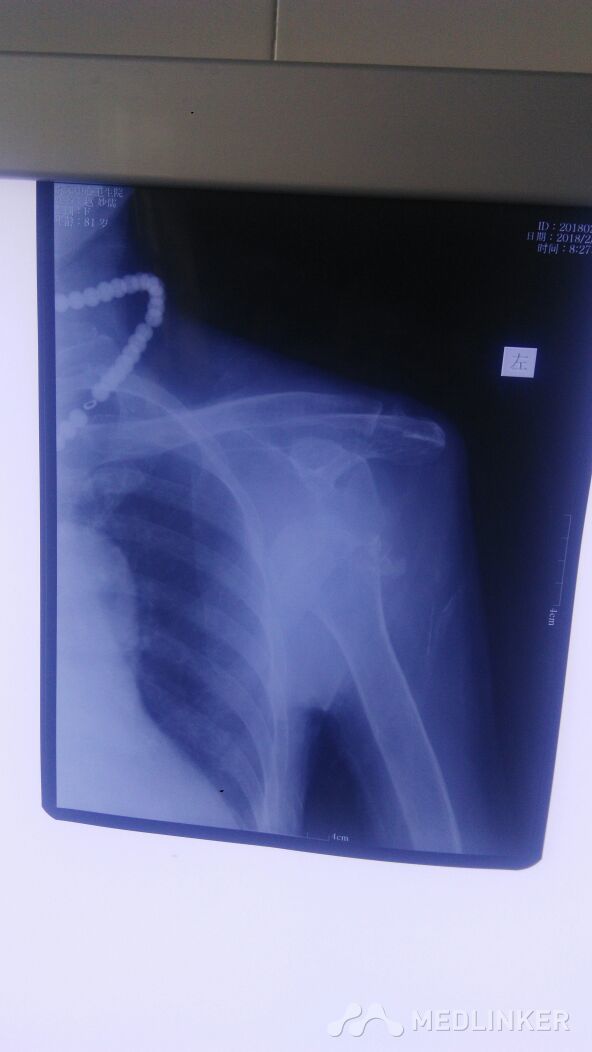

肩关节脱位并骨折

陈旧性肱骨骨折伴肩关节脱位1例

肩关节脱位

肩关节半脱位?